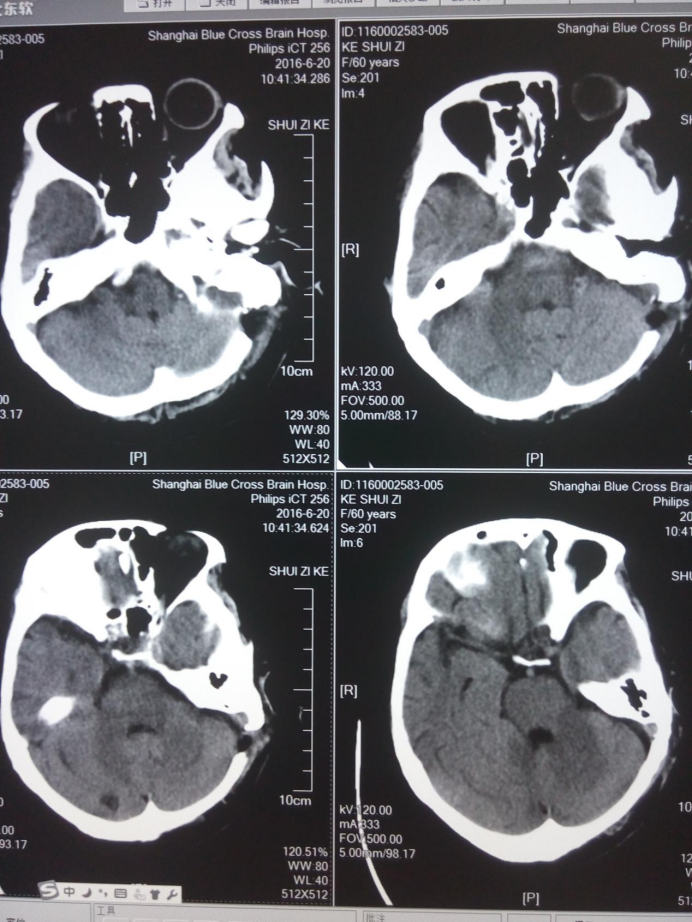

舌咽神经微血管减压术后头部CT检查

手术治疗是治疗舌咽神经痛优先选用的治疗方法,术中所见血管对迷走神经的压迫较舌咽神经更为严重,对迷走神经及舌咽神经行充分减压后患者上述症状完全消失。